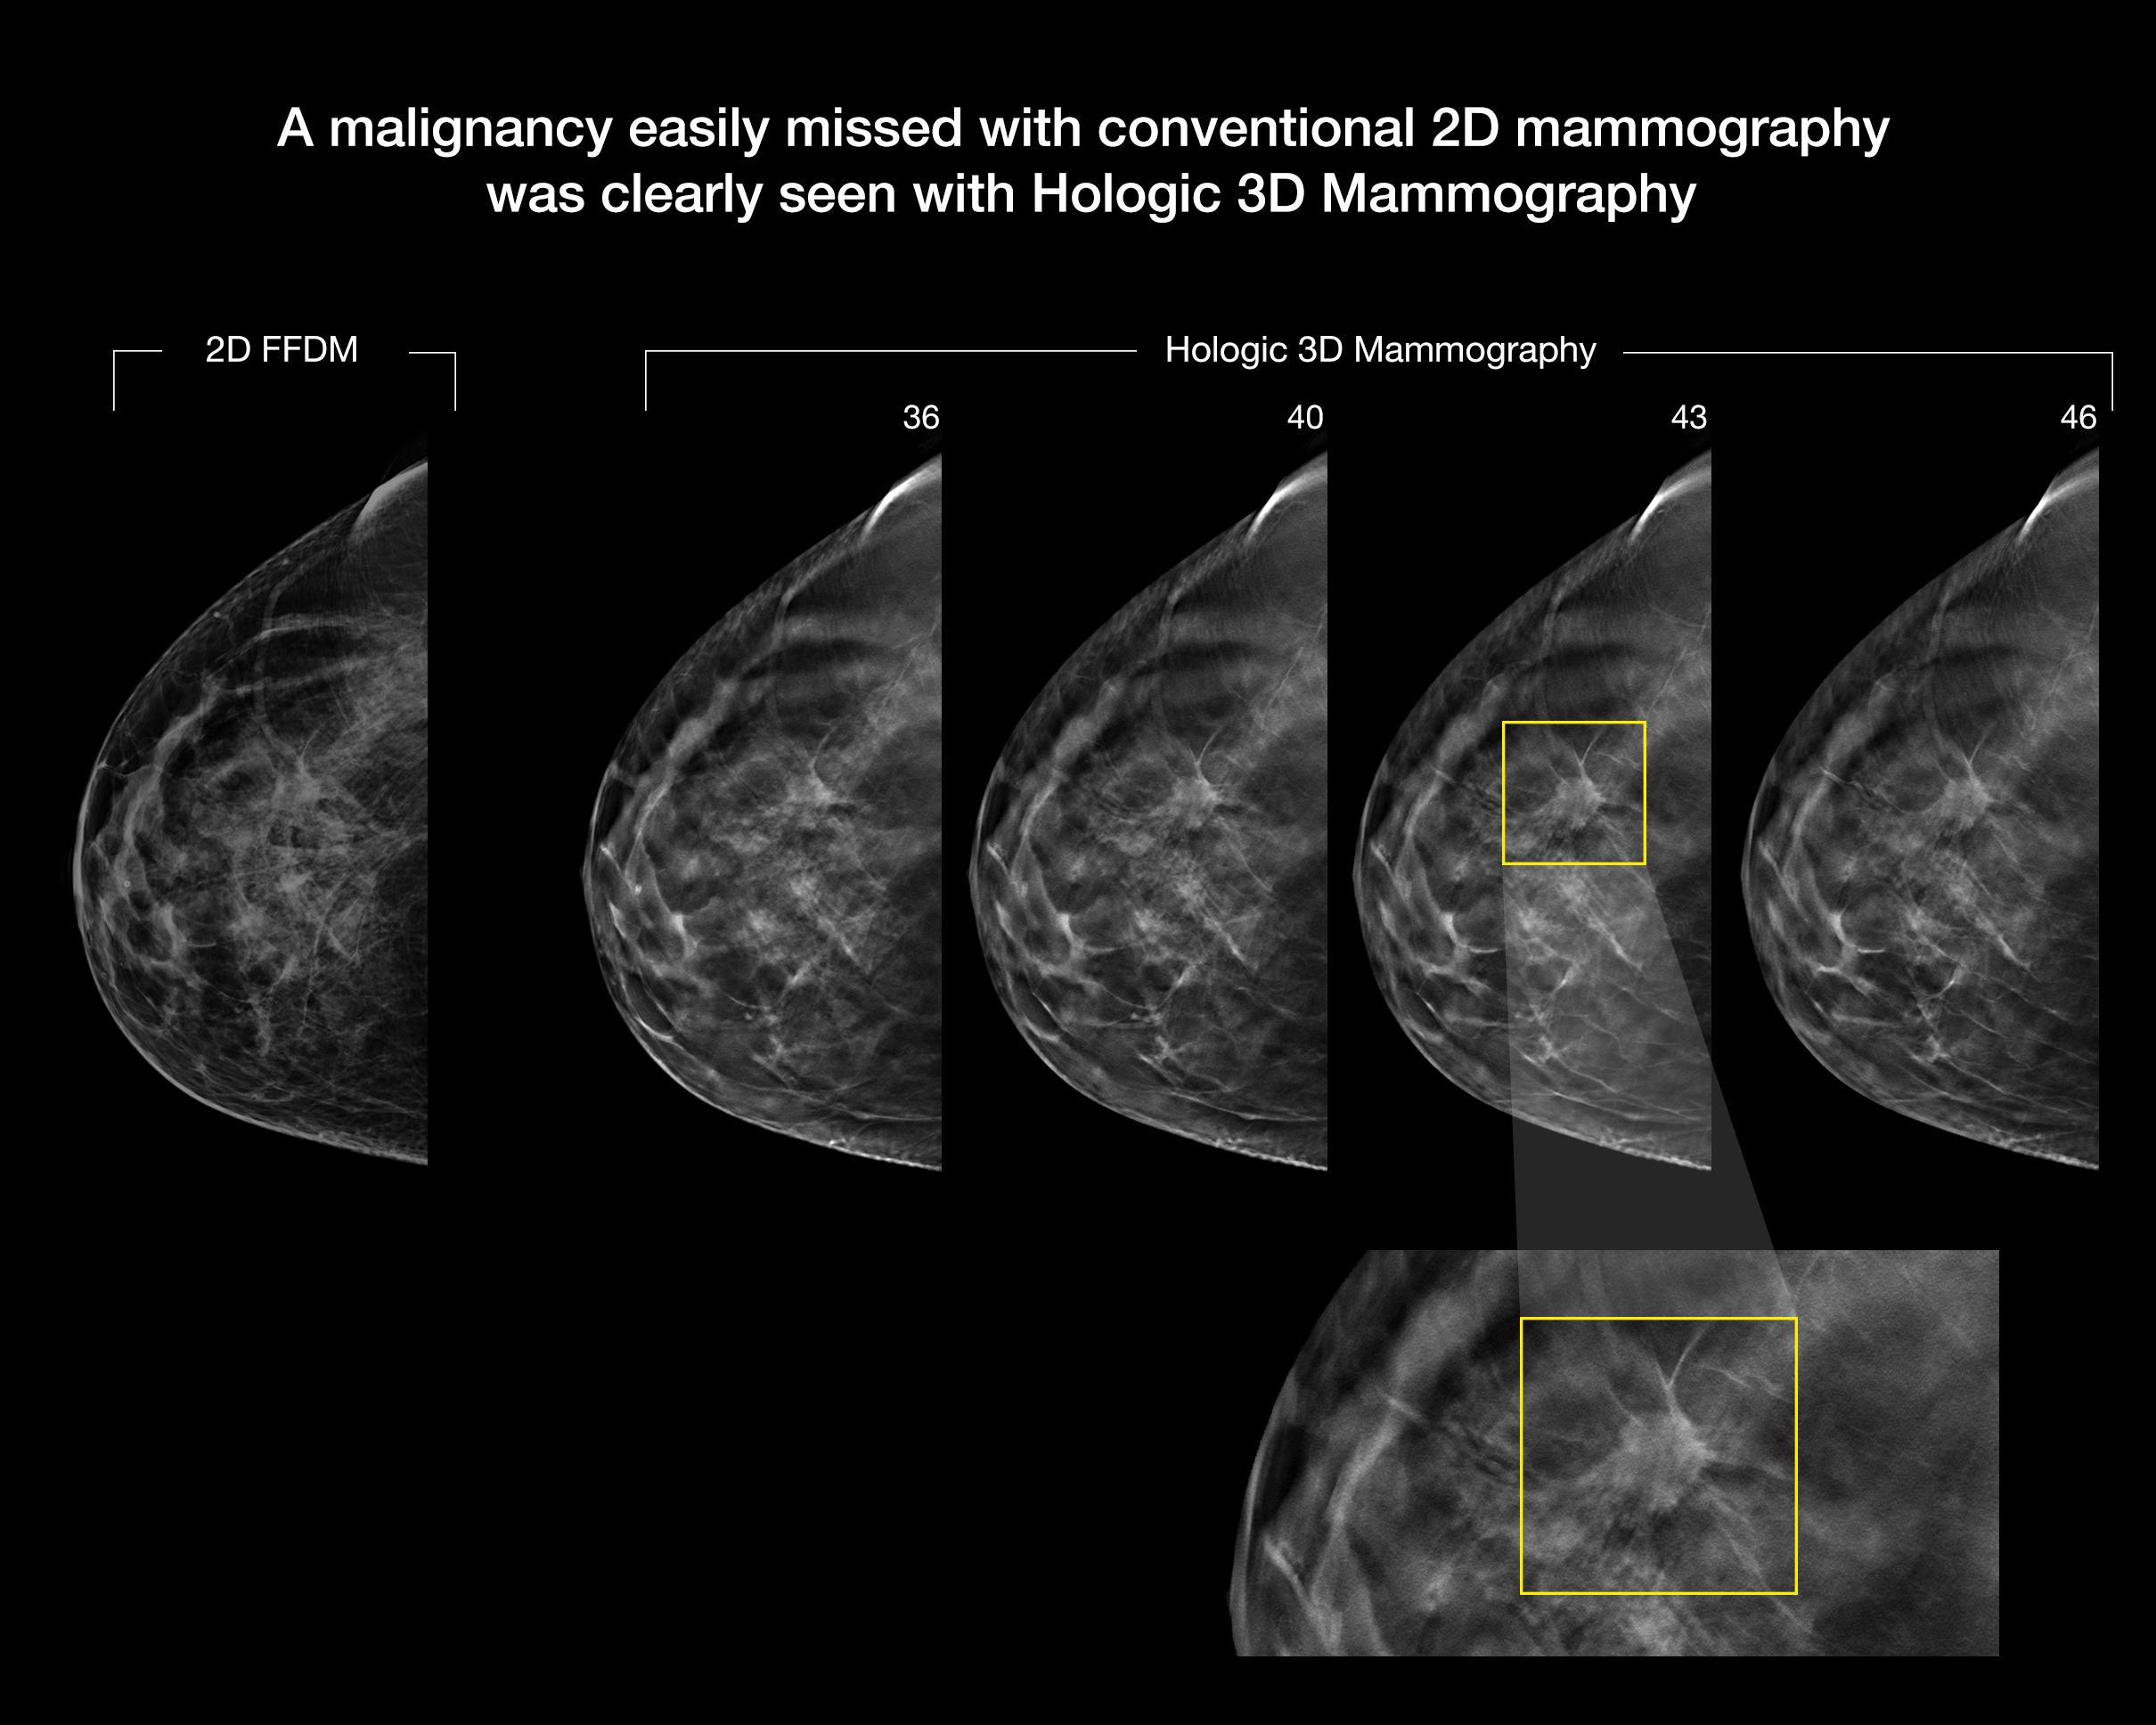

Designed to be the fastest, highest resolution breast tomosynthesis system, ever.

The new 3Dimensions mammography system matches the unrivaled performance of our Genius 3D Mammography™ exam, which is more accurate than conventional 2D mammograms, detecting 20%-65% more invasive breast cancers.1-8 Breakthrough improvements transform the patient experience without compromising speed or accuracy.

Better visibility

Designed to improve visibility of fine details for greater diagnostic confidence.*